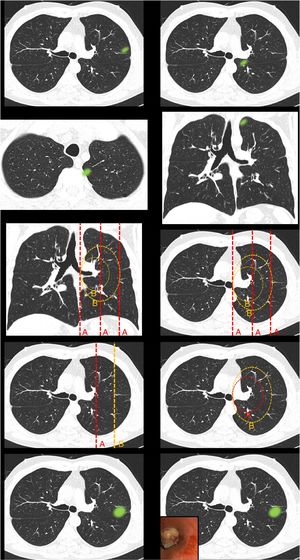

Definition of centrality (Fig. 1): this block evaluated the uniformity of criteria defining centrality.

Fig. 1.This block evaluated the uniformity of criteria defining centrality. Image 1: In your opinion, is the site of the nodule: central/peripheral? Image 2: In your opinion, is the site of the nodule: central/peripheral? Images 3a and 3b: In your opinion, is the site of the nodule: central/peripheral? Image 4: Which of the following lines best defines centrality? A lines/B lines. Image 5: Which of the following lines best defines centrality? A lines/B lines. Image 6: Which of the two lines demarcates a central tumor? A line (inner third)/B line (inner two thirds). Image 7: Which of the two lines demarcates a central tumor? A line (inner third)/B line (inner two thirds). Image 8: In your opinion, is the site of the nodule: central/peripheral? Image 9: In your opinion, is the site of the nodule: central/peripheral?

Definition of centralityAlmost half of the respondents selected “lesions in contact with hilar structures” (49.7%) as the definition of central tumor location (Table 1 [Question 1]). The lines most often selected to delimit centrality were B lines (concentric lines arising from the pulmonary hilum) (89%) (images 4 and 5). The “peripheral lesion positive control” image (image 1) was classified as peripheral by all respondents while the “central lesion positive control” image (image 2) was classified as central by three-quarters of the respondents. The image selected as “SEPAR central lesion positive control” (images 3a and 3b) was mostly classified as peripheral (71.1%). Most respondents voted to restrict centrality to the inner third of the hemithorax, instead of the inner two thirds for both A lines (image 6) (310 [72.3%]) and B lines (image 7) (339 [79%]). The presence of an endobronchial lesion influenced the classification of a lesion as central, since only 7% of respondents initially classified an image (image 8) as such, yet this proportion increased to 36.1% (image 9) when information from an endobronchial image was added (Fisher’s exact test p < 0.01). Unlike other questions, statistically significant differences between specialties were observed for this image (Fisher's exact test p < 0.01) (Table 1).

The nodule image shows a peripheral lesion (“peripheral lesion positive control”) as defined by the ESTS and ACCP, irrespective of the dividing lines to be used (lines parallel to the midline [A lines] or lines concentric to the hilum [B lines]).

The nodule image shows a central lesion (“central lesion positive control”) as defined by the ESTS and ACCP, irrespective of the dividing lines to be used (A lines or B lines).

The nodule image shows a central lesion according to the SEPAR definition of central tumor location (“SEPAR central control”).

The image shows A lines and B lines in an axial CT slice and respondents should choose between the inner third and inner two thirds as the dividing line for classification of lesions.

The image shows B lines in an axial CT slice and respondents should choose between the inner third and inner two thirds as the dividing line for classification of lesions.